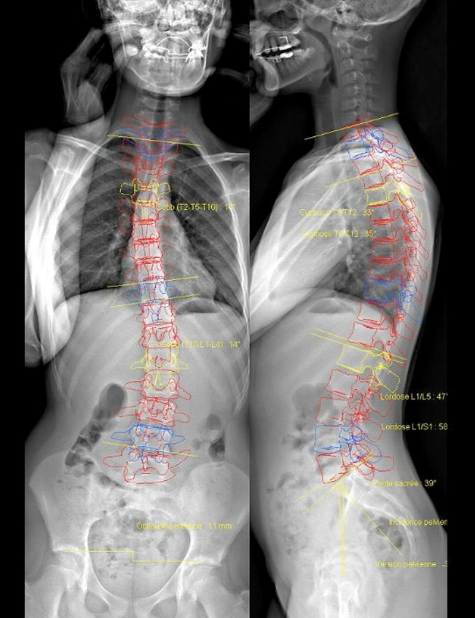

Cette avancée technologique représente une véritable révolution dans le domaine de l'imagerie, propulsant notre établissement vers de nouveaux sommets. Cette technologie d'imagerie révolutionnaire offre une perspective entièrement nouvelle sur l'imagerie Musculo Squelettique, offrant des avantages distincts par rapport aux méthodes traditionnelles en particulier pour l'analyse des différents angles du squelette en position debout.

L'une des caractéristiques les plus remarquables de la cabine EOS est sa capacité à produire des images tridimensionnelles du squelette de haute qualité, en position debout. Cette visualisation avancée permet aux médecins d'analyser avec précision les structures osseuses et les articulations et leurs différents angles, offrant ainsi une compréhension plus complète des morphologies osseuses et des anomalies anatomiques.

La cabine EOS se distingue par sa capacité à produire des images d'une netteté et d'une précision exceptionnelles. Grâce à une technologie avancée de balayage, elle capture des images radiographiques haute résolution avec une exposition extrêmement faible aux rayons X, réduisant ainsi considérablement l'exposition aux radiations pour les patients et le personnel médical.